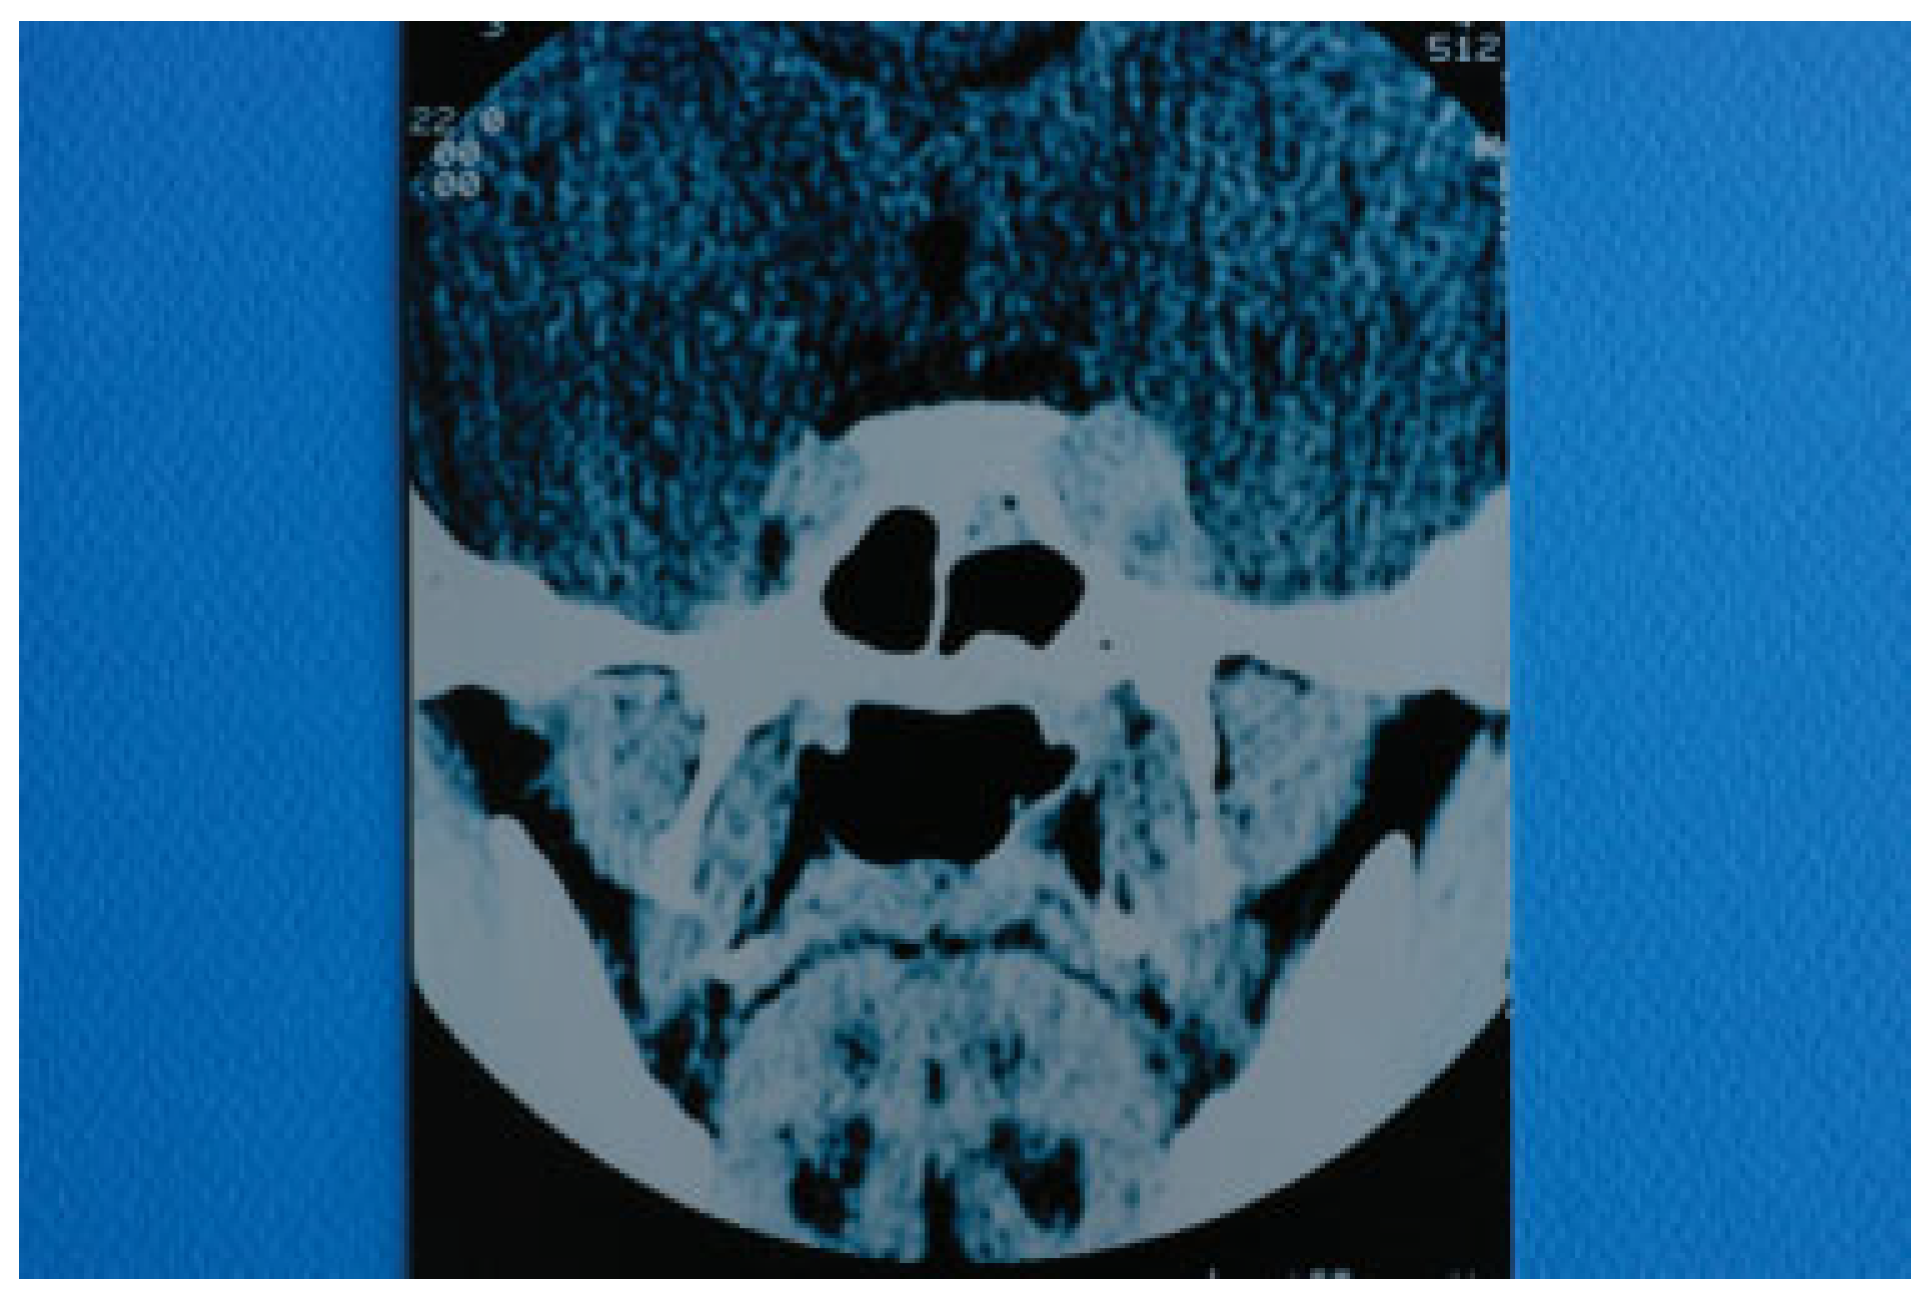

On the 21st postoperative day (31st postinjury day), the patient presented with marked left exophthalmos, periorbital swelling and ecchymosis, ptosis of the upper eyelid, ocular pain, nausea, and vomiting. The condition was diagnosed as periorbital cellulitis and double intravenous antibiotic therapy was initiated (Figure 2). Computerized tomography (CT) of the left orbit disclosed a mild inflammatory reaction around the miniplate in the infraorbital rim and in the region of the orbital floor. CT also revealed the presence of dilation of the upper ophthalmic vein but this finding was not further evaluated at that time (Figure 3). The clinical presentation of the patient was attributed to infection of foreign materials that were placed during the operation and therefore the plate and the lyophilized dura were removed.

Two days after the removal of the foreign materials, there was a dramatic deterioration of the patient’s clinical presentation with intense ocular pain, worsening of exophthalmos, nausea, and vomiting. The patient also complained of “strange sounds in the cranium like water tapping.” Clinical examination revealed a systolic thrill on palpation of the left eye and a systolic wheeze on auscultation of the left frontal and temporal area. Measurement of intraocular pressure was subsequently performed and an intraocular pressure of 13 mm Hg in the right and 24 mm Hg in the left eye were recorded. Visual acuity was measured 5/6 vision and fundus examination revealed venous dilatation without further pathologic signs. The finding of intensive dilation of the left upper ophthalmic vein in the primary computed tomography was reevaluated and a posttraumatic CCF was suspected and included in the differential diagnosis. A new CT of the left orbit was ordered which revealed a threefold dilation of the cavernous sinus (Figure 4). The digital subtraction angiography (DSA) confirmed the diagnosis of CCF as it revealed a dilation of the cavernous sinus, a blood shunt between the lumen of the internal carotid artery and the cavity of the cavernous sinus, and a dilation of the upper ophthalmic vein (Figure 5).

Figure 3. Computed tomography of the skull taken with intravenous contrast medium. Dilation of left superior ophthalmic vein is depicted.

Figure 4. Computed tomography of the base of the skull illustrating a threefold dilation of the left cavernous sinus.